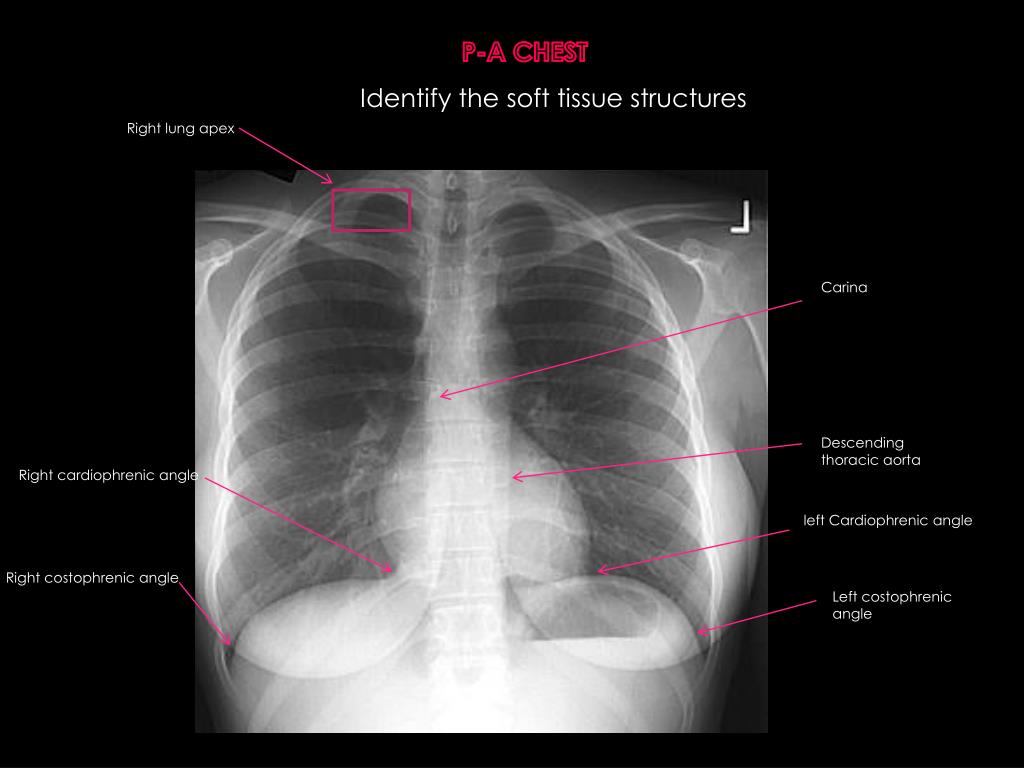

7. P-A CHEST Identify the soft tissue structures

8. P-A CHEST Identify the soft tissue structures Right lung apex Carina Descending thoracic aorta Rightcardiophrenic angle left Cardiophrenic angle Right costophrenic angle Left costophrenic angle